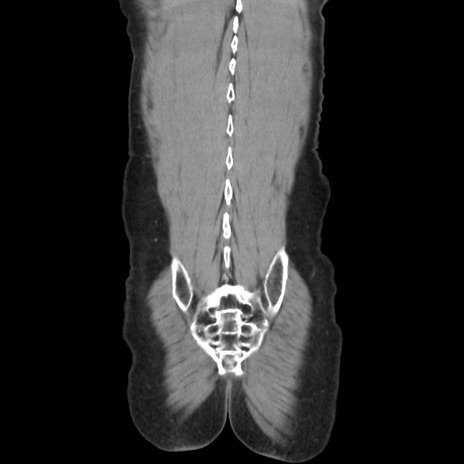

症例37(冠状断像)

【症例】40歳代 男性

【主訴】腹痛

【現病歴】4時間ほど前に電車に乗車中に臍部上より腹痛出現。徐々に増悪し起立困難となり、救急外来受診。生ものは数日食べていない。今朝お雑煮を食べた。

【身体所見】BT 36.8℃、BP 117/84mmHg、HR 91/min、SpO2 97%、苦悶様、腹部:臍上部広範囲圧痛あり、反跳痛±

【データ】WBC 8100、CRP 0.03